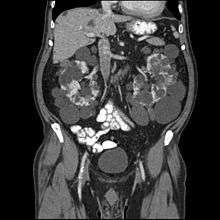

Additional images

Adult polycystic kidney.